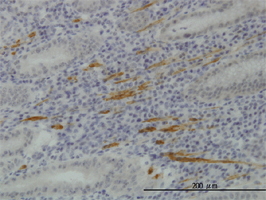

CD169, Monoclonal Antibody (Cat# AAA12206)